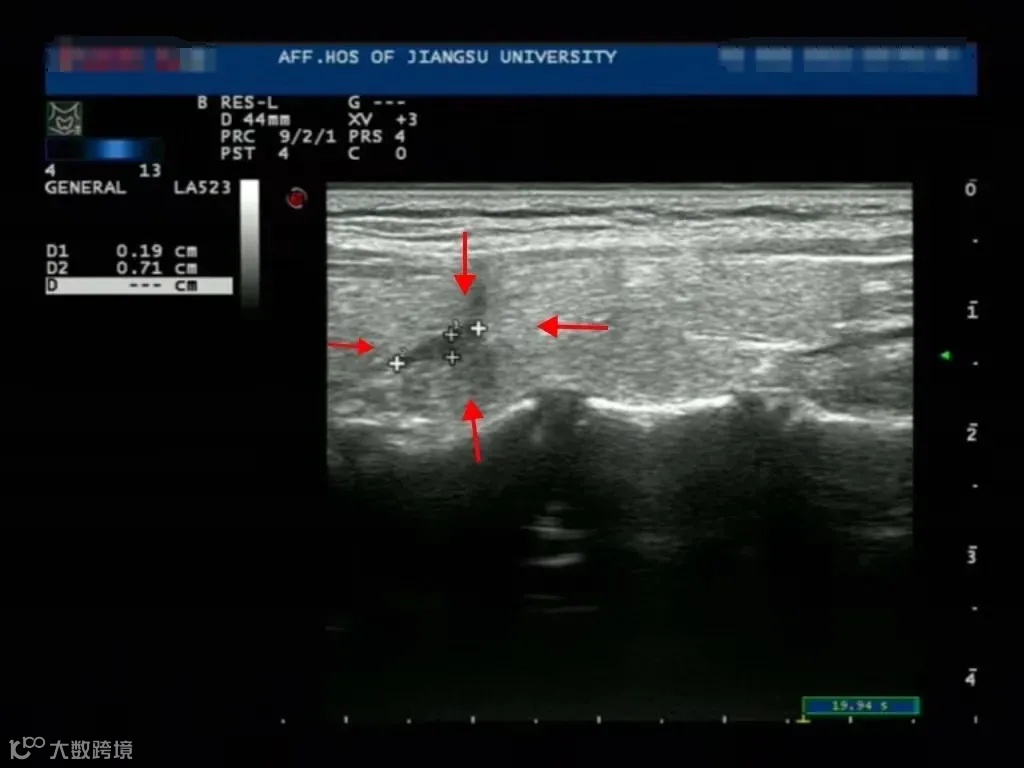

治疗后

治疗后3个月 结节明显缩小

经过详细地了解,王女士决定接受消融治疗。整个治疗过程只需几十分钟,术后便可下床活动,术后2小时便可进食,术后第二天即可办理出院。